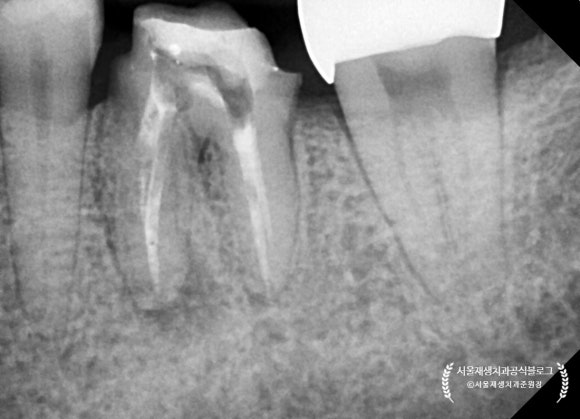

현미경을 이용해서

뿌리 끝까지 청소를 해 내려간 결과,

노랗고 빨간 고름이 뿌리 끝에서 퐁퐁퐁 솟아나는 것을 관찰할 수 있었습니다.

딱딱한 뼈 안에 고름이 차오르고 있었으니

얼마나 아팠을까요?

치아 내부에 소독약제를 도포하고 약처방을 해드린 후

두번째와 뒤이은 세번째 내원날에는

모든 신경들을 뿌리 끝까지 청소하기 위해 노력했습니다.

나중에라도 통증을 일으킬 수 있는 원인을

준원장의 정성에 하늘이 감동하셨는지,

아래 어금니의 모든 신경을 깨끗하게 청소하는데 성공하였고,

고름도 더 이상 나오지 않았습니다!

세 번의 내원만에 얻어진 값진 결과입니다.

치아 내부에 소독 약제를 뿌리 끝까지 도포하였습니다.